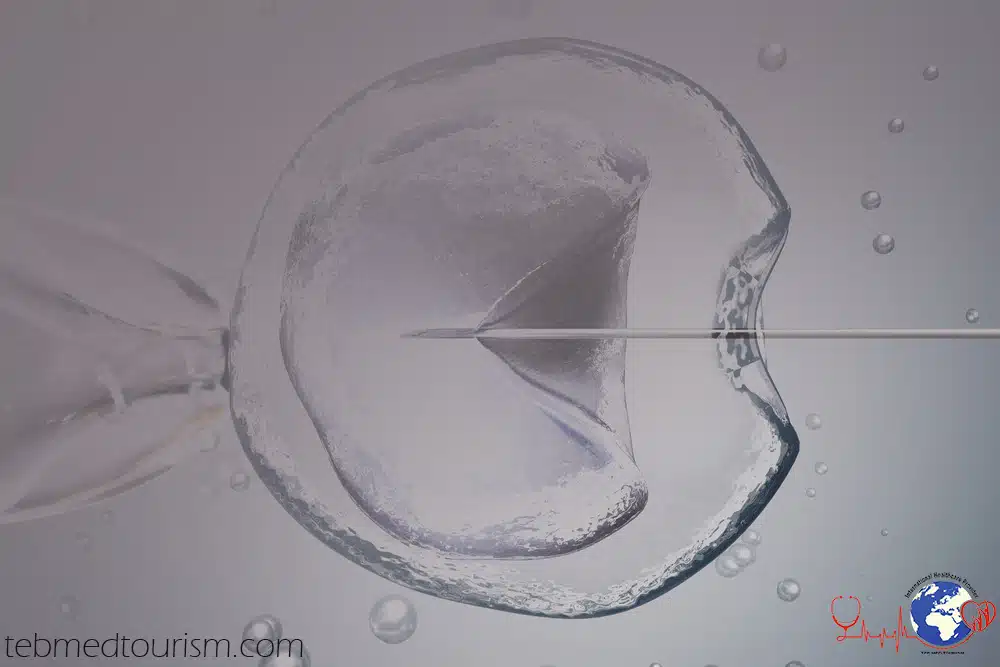

- جمع البويضات: يتم تخدير الزوجة عند جمع أكبر عدد ممكن من البويضات باستخدام مسبار موجه بالموجات فوق الصوتية ، لجمع أكبر عدد ممكن من البويضات من كلا المبيضين.

- الإخصاب في المختبر: يتم تلقيح البويضات بالحيوانات المنوية وتوضع بعدها في سائل مغذي ( وسط مزرعه ). وعادة ما يحدث الإخصاب في غضون 24 ساعة.